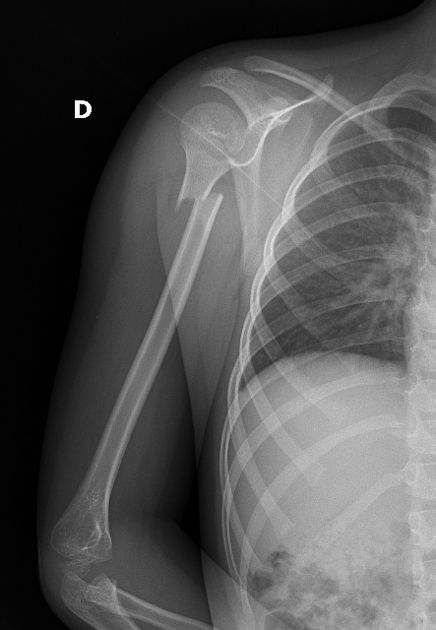

⚡Проксимальный перелом плечевой кости⚡

Данные Пациента Возраст: 6 лет Пол: Женский ❗❗Такие переломы достаточно редкие в данном возрасте ❗❗ Обычно переломы такого типа лечат консервативно. Переломы в проксимальной части плеча могут сочетаться с вывихом в плечевом суставе, особенно у детей. #ргснимок

❗❗Такие переломы достаточно редкие в данном возрасте ❗❗

Обычно переломы такого типа лечат консервативно.

Переломы в проксимальной части плеча могут сочетаться с вывихом в плечевом суставе, особенно у детей.